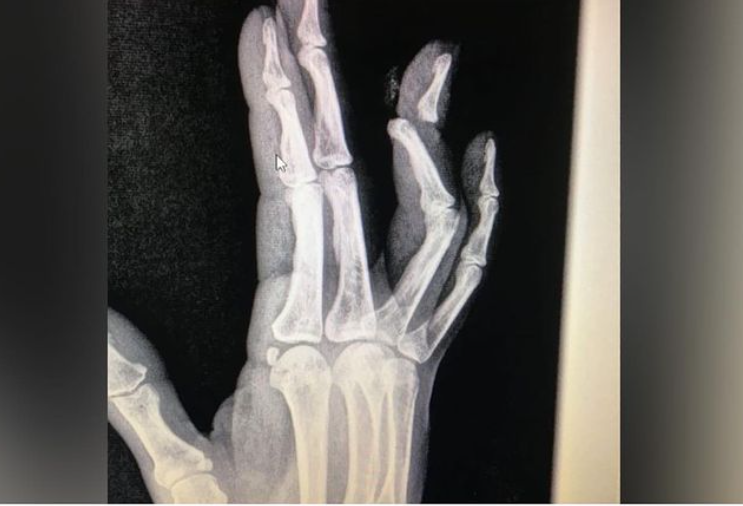

Бишкек шаарында кыз үйлөнүүдөн баш тарткан жигитинин сөөмөйүн сындырып, сабап салды. Бул тууралуу маалыматты Бишкек шаардык тез жардам кызматынын "Тез жардамдагы дарыгер" бейрасмий аккаунту жазып, жарыялап чыкты.

Жигиттин бул чечими кыз-жигиттин ортосунда түшүнбөстүктү пайда кылып, кыз жигиттин манжасын сындырып, сабап салган.

Окуя болгон жерге тез жардам кызматы келип, жабырлануучуга керектүү жардам көрсөтүлгөн.